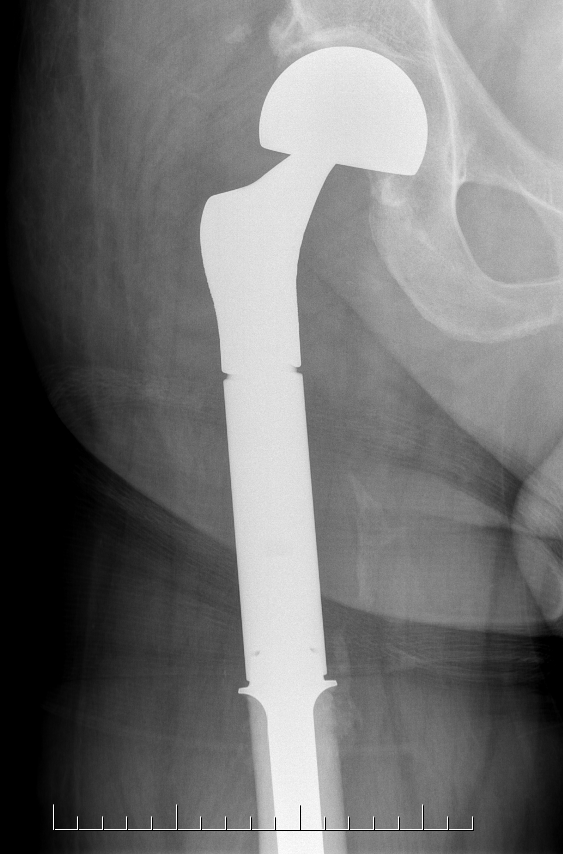

High grade / Wide resection

Wide resection

- hemipelvectomy